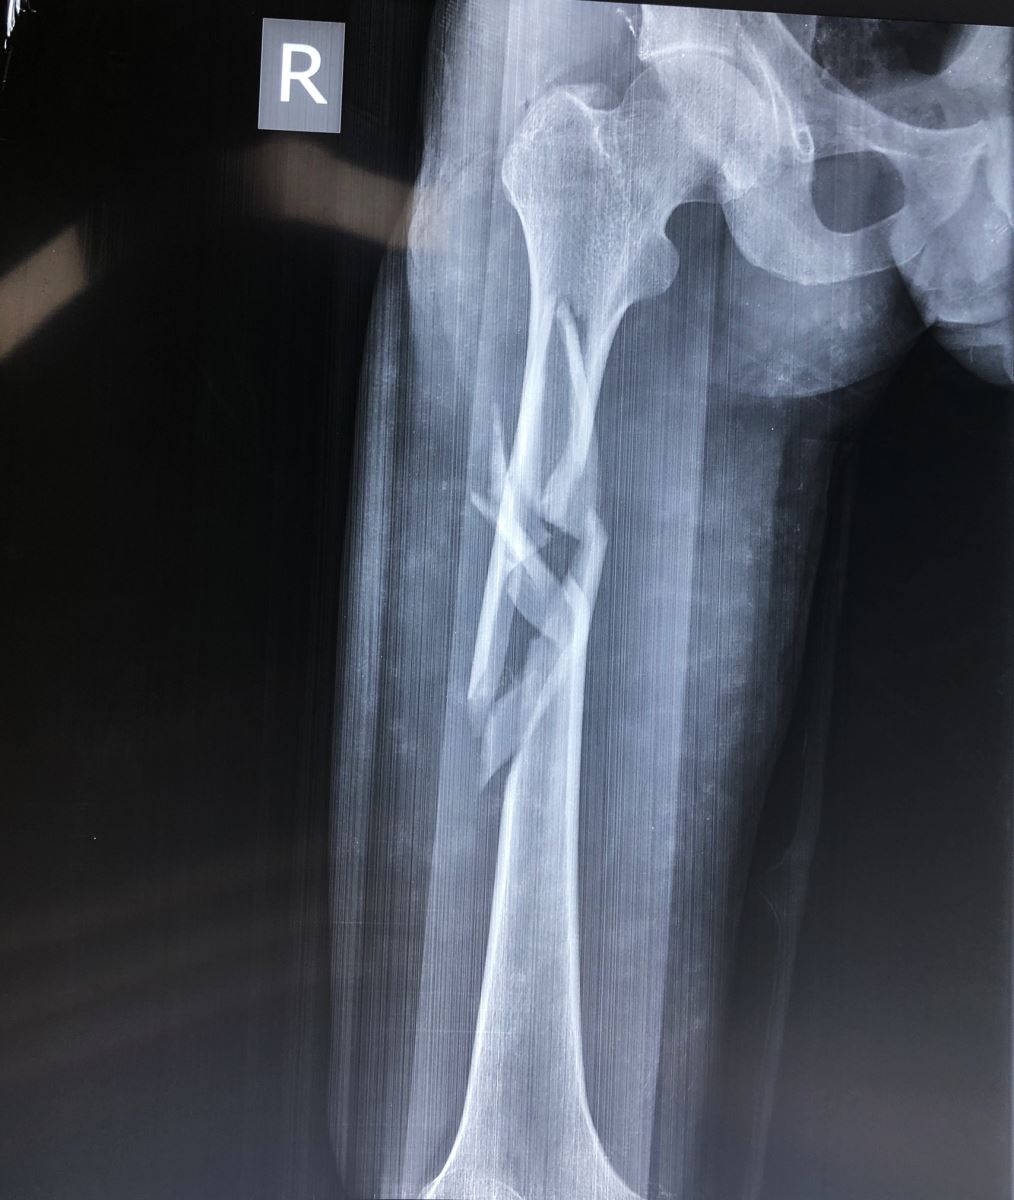

1.2. Đường gãy

Gồm có gãy ngang, gãy chéo, gãy xoắn, gãy 2 ổ hoặc gãy vụn.

- Đường gãy ngang: Thường do gập góc, dạng gãy này sau khi nắn tốt thì thường vững chắc hơn các dạng gãy khác.

- Đường gãy chéo, xoắn: Thường do gập góc kèm theo vặn xoắn cơ thể. Dạng gãy này không vững chắc sau khi nắn

1.3. Sự di lệch

Tuỳ theo vị trí gãy và có các hình thái di lệch khác nhau. Các di lệch thường gặp là gập góc, lệch sang bên, chồng lên nhau, xoay ngoài của đoạn gãy xa.

3. CHẨN ĐOÁN HÌNH ẢNH (X-QUANG)

Mặc dù chẩn đoán bằng X quang là cần thiết, nhưng cần khám kỹ lâm sàng để tránh bỏ sót thương tổn. Một số trường hợp bỏ sót trật khớp háng trong gãy thân xương đùi vì chỉ chụp giới hạn ổ gãy. Do vậy để có một phim X quang tốt cần chú ý:

- Chụp lấy được 2 khớp của đầu xương gãy ít nhất hai bình diện thẳng và nghiêng.